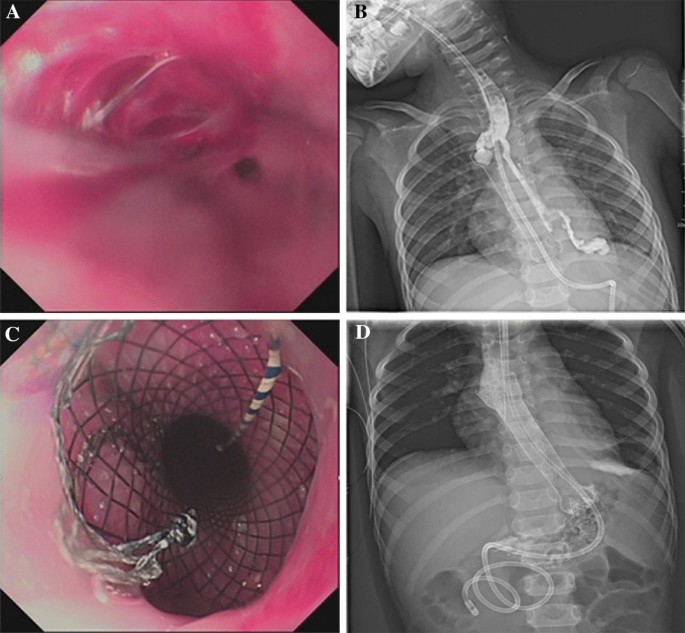

Stenting procedure

Illustration of fully covered self-expandable metal stent replacement. (A) Endoscopic view of the preoperative stricture with the zebra super-hard guide wire inserted into the stomach; (B) Under the guidance of the guidewire, FCSEMS was delivered to the stricture site through the stent delivery device; (C,D) Opening the safety lock and pushing the rear handle forward slowly to release the stent; (E,F) The stent was released and the lumen enlarged after FCSEMS placement.

Two patients with achalasia of cardia (cases 11 and 12) showed remarkable improvement in the symptoms of vomiting (Fig. 4B,C) without the need for further stent placement. Two patients (cases 2 and 11) presented symptoms of vomiting and chest pain 2–3 days after stenting, which were relieved by conservative management without stent removal. Three patients (cases 5, 9 and 10) developed restenosis 3 months after stent removal, but the degree of stenosis had been significantly mitigated compared to before stenting and the lumens at the narrowing were significantly enlarged, with improvement in swallowing difficulty after the new stents were placed (Fig. 7B).

More specifically, 2 patients (cases 5 and 9) failed to meet the follow-up schedules due to parental reasons, but were subsequently readmitted for chest pain and discomfort symptoms that occurred again about 3 months after stent placement. To treat these patients, their stents were removed after the finding of inflammatory granulation tissue hyperplasia at the lower end of the stent in case 5 (Fig. 7A) and stent embedding in case 9 (Fig. 7C). Fortunately, the embedded stent was removed successfully with the help of biopsy forceps (Fig. 7D), but both cases still needed additional stent and balloon dilatation treatment before their symptoms were completely relieved.